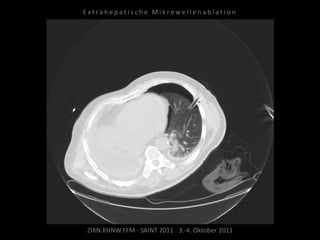

Patient: Männlich, 64 Jahre

Diagnose: Bronchial-Ca rechts, Z.n.

Pneumonektomie,

neu aufgetretene, solitäre, im Verlauf

progrediente Metastase im Oberlappen

links.

Situation:

Nur eine Lunge und in dieser eine

(kleine) Metastase.

Ablation am 27.11.2010

1 Nadelposition.

Kontrolle nach MWA:

Parenchymeinblutung, Pneumothorax.

Noch im CT Anlage einer Pleuradrainage.

Patient am Abend beschwerdefrei.